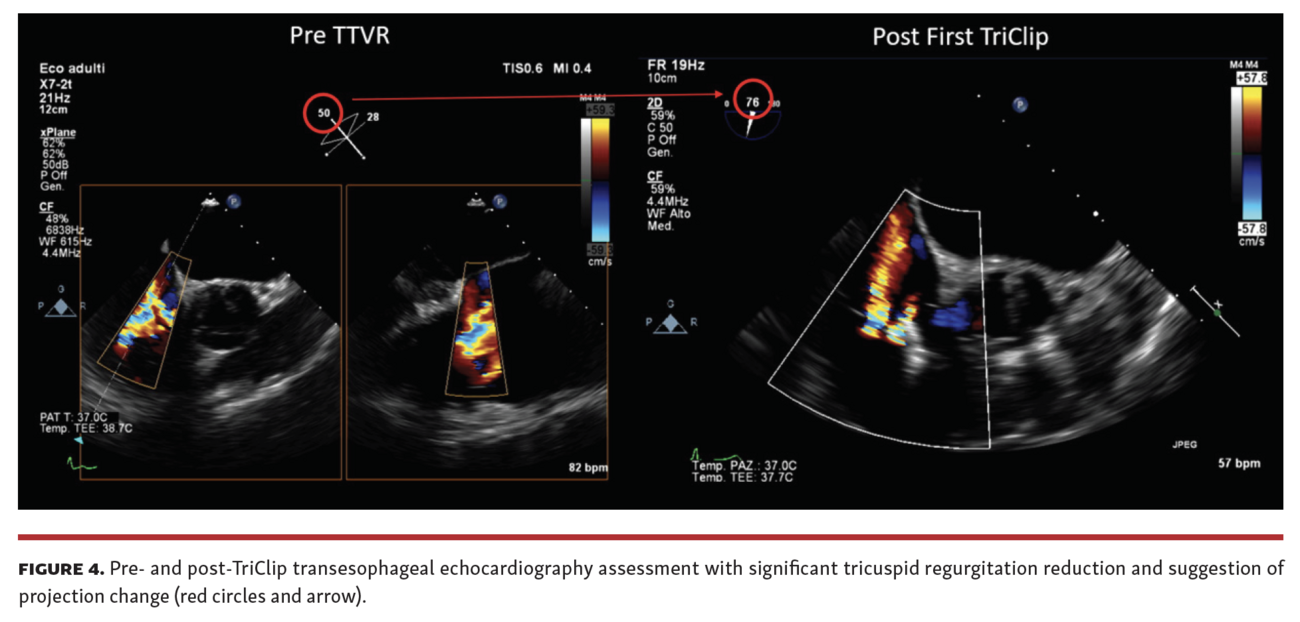

The preprocedural cardiac magnetic resonance (CMR) showed a right ventricular end-diastolic volume index (RVEDi) of 79 mL/m2, right ventricular end-systolic volume index (RVESi) of 27 mL/m2, tricuspid regurgitant volume (TRV) of 56 mL, and tricuspid regurgitant fraction (TRF) of 67% (Figure 3). Due to the patient's history of breast cancer radiotherapy and high surgical risk, the heart team preferred a transcatheter approach as the treatment option. The first TriClip (Abbott Vascular) was successfully implanted in the anteroseptal commissure, determining annulus size reduction and the subsequent necessity of transesophageal echocardiographic projection change to assess the result due to acute reshaping (Figure 4 and Figure 5; Video Series). A second TriClip was implanted in the anteroseptal commissure, highlighting the changes in the valvular plane and cardiac axis (Video Series). Residual TR was trivial (Video Series). The acute remodeling was confirmed at the CMR follow-up (Figure 6), with significant volume and TR reductions (RVEDi, 39 mL/m2; RVESi, 18 mL/m2; TRV, 8 mL; and TRF, 23%).